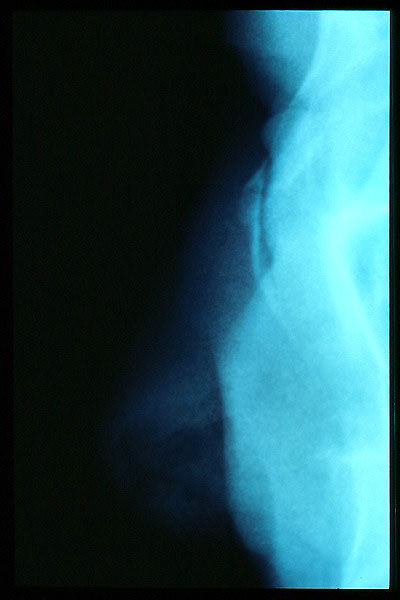

Artrosis cervical.